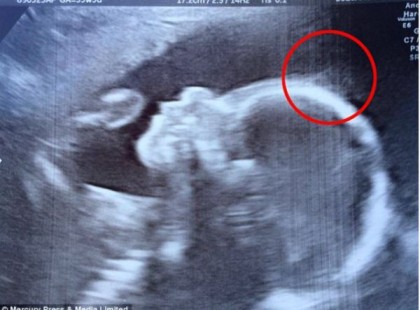

Az orvosok megrökönyödnek, amikor az ultrahangon valami furát vesznek észre a kicsi fején: Így néz ki napjainkban a kisbaba!

Holly nagyon különleges kisbaba! Már a 20 hetes ultrahangon észrevette az orvos, hogy valami olyasmi van a fején,...